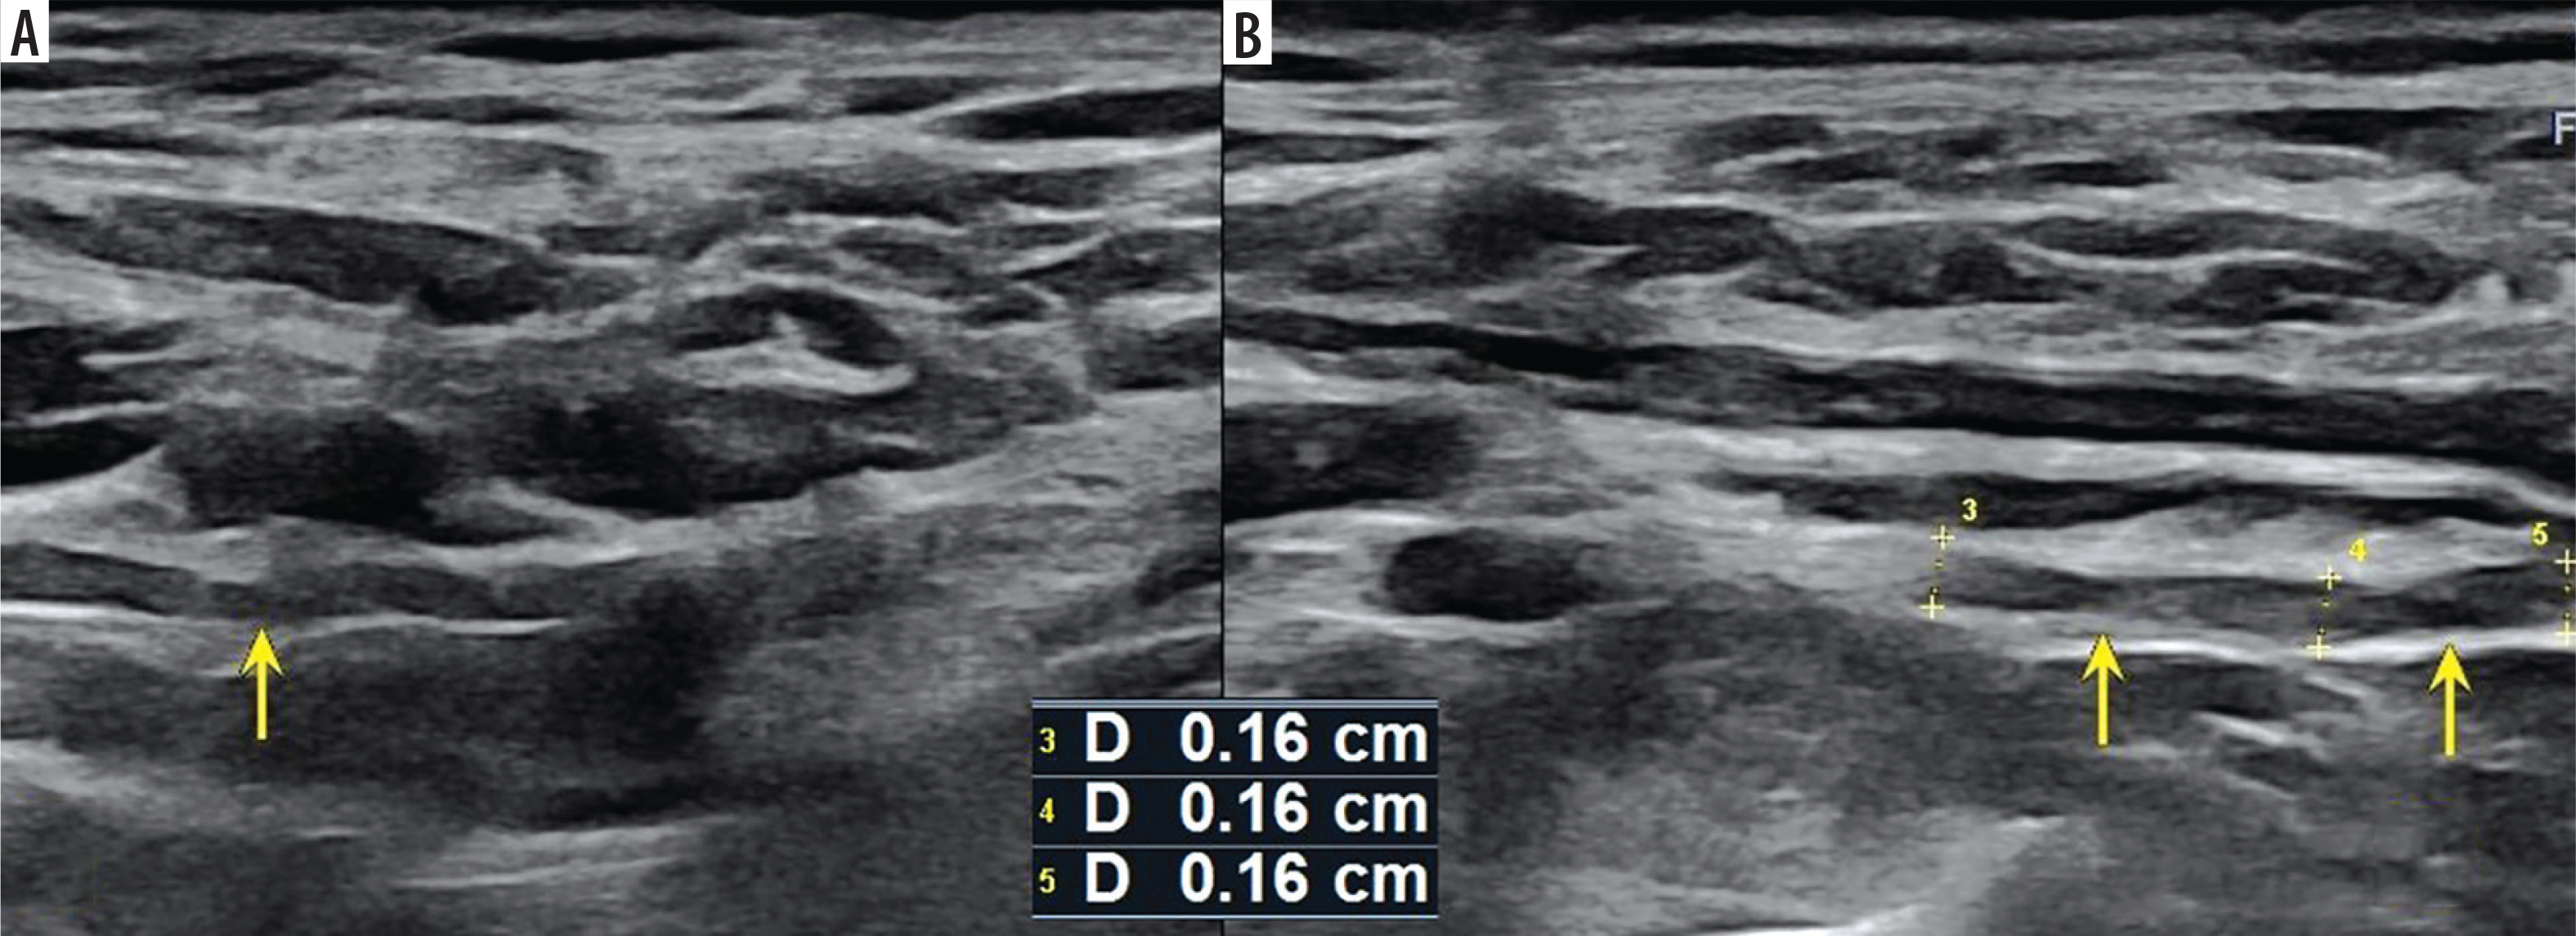

Figure 2

High-resolution ultrasound image of LTN torsion with an ”hourglass-like” constriction sign – marked with arrow (A) with comparison to the asymptomatic side (B) in 50-year-old patient with Parsonage-Turner syndrome. Images obtained by author with a 3-19 H linear probe of the Alpinion XCube90